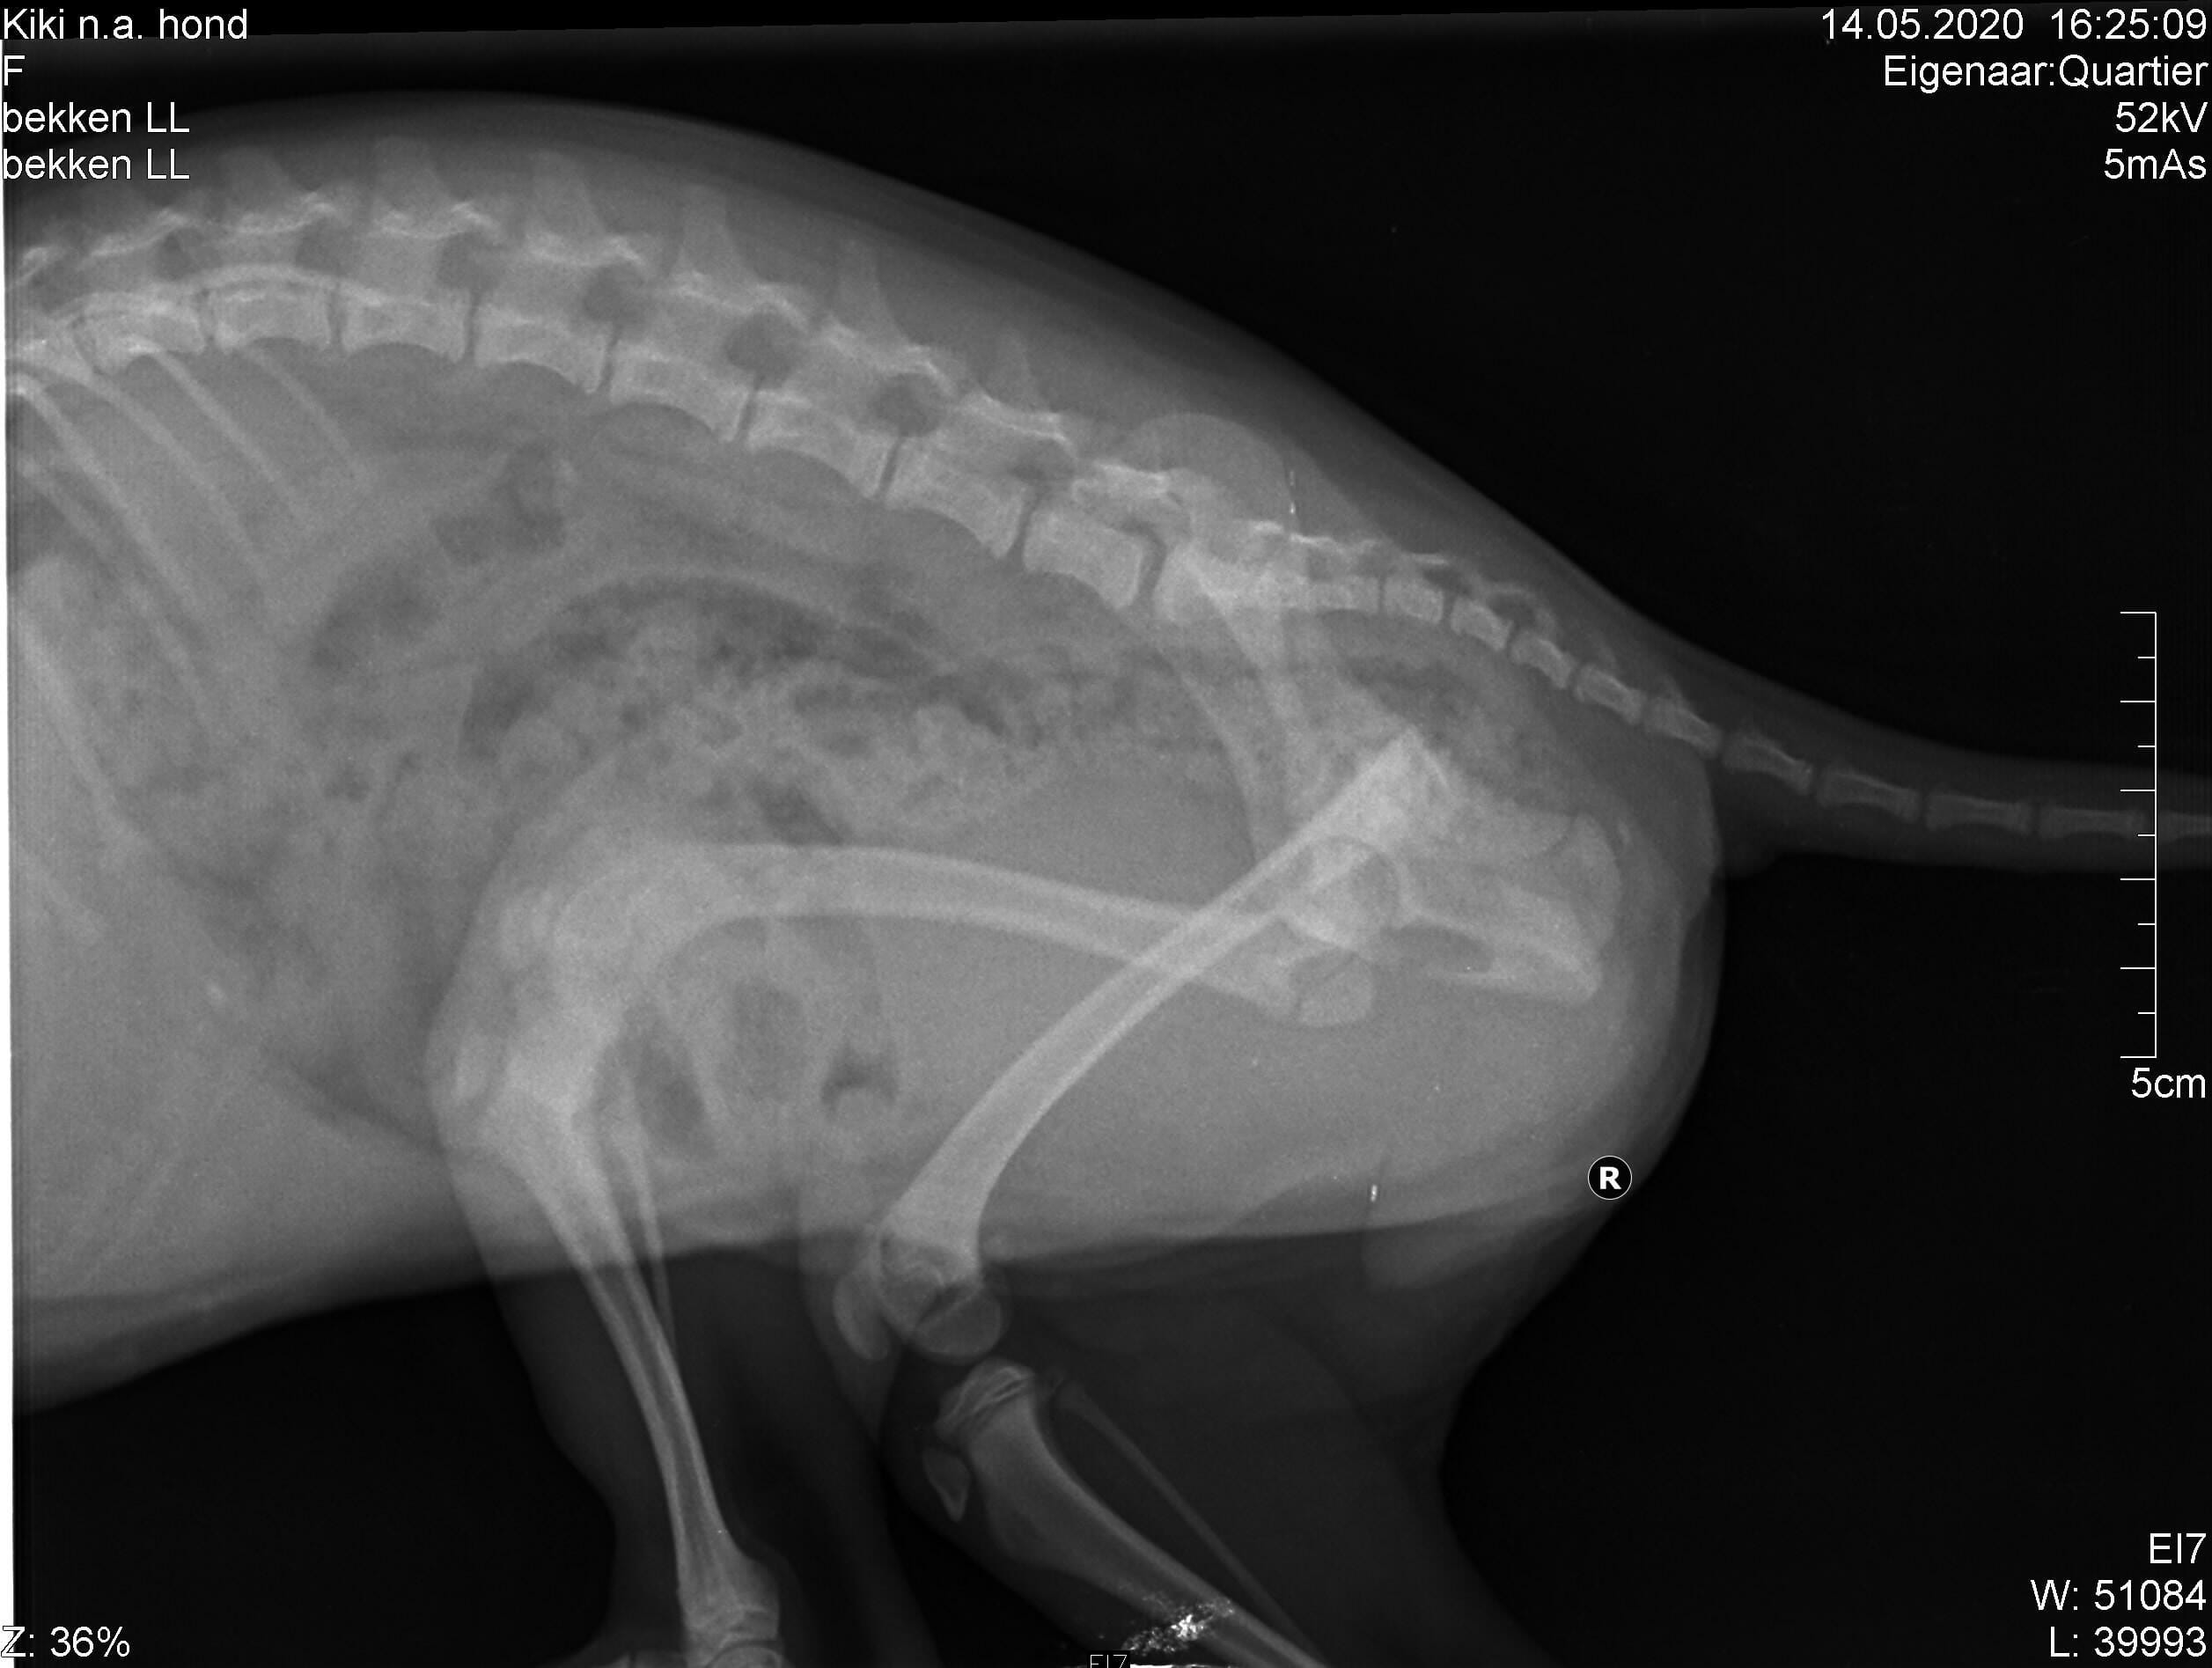

Pet's info: Dog | Mixed Breed Small (up to 22lb) | Female | unspayed | 4 months and 3 days old | 8.15 lbs

best treatment on a small dog with broken trochanter major. Vets here want to remove the top small broken piece on Monday. I want to know of that procedure is normal. They say it is very difficult to attach it again with small dogs. They told me it would be better that way and the doig will be running again in a few months.

Yes, this is a normal and common procedure for this type of injury in small dogs. The procedure of removing the femoral head (greater trochanter) is referred to as a femoral head osteotomy (FHO). I hope that Kiki has a smooth recovery!

Hello and thank you for contacting Petco Pet Education Center, formerly Petcoach. Femoral head excision is a very common surgery for fractures of the head of the femur, like this. It is relatively easy to do, and most of the dogs do very well after the surgery, If Kiki is a small breed dog, most likely she will be fine and in a few months time you will not be able to notice which leg she was operated on. Fixing a fracture of this part of femur is possible but it would involve, in my opinion placing an intramedullar pin and a plate or wire. It would be complicated but a specialist in orthopaedics should be able to do it.